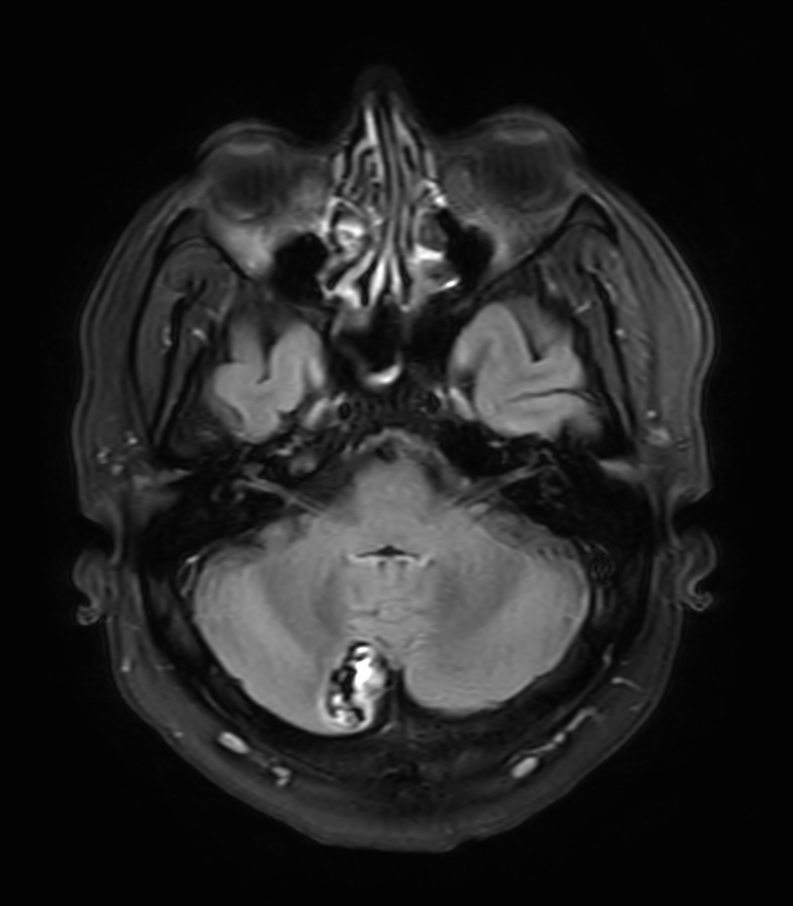

Patient with a lesion in the cerebellum. The ExamCard includes Compressed SENSE to accelerate the entire exam and techniques for motion reduced imaging (MultiVane XD), 3D imaging to acquire high resolution data in multiple directions, 3D susceptibility weighted imaging (SWIp), angiography sequences (Time-of-Flight and Contrast-Enhanced MRA with both arterial and venous phases), DTI with MultiBand SENSE to acquire a high number of diffusion directions in a short scan time and EPIC Brain to bring down any residual distortion.

T2w TSE MultiVane XD